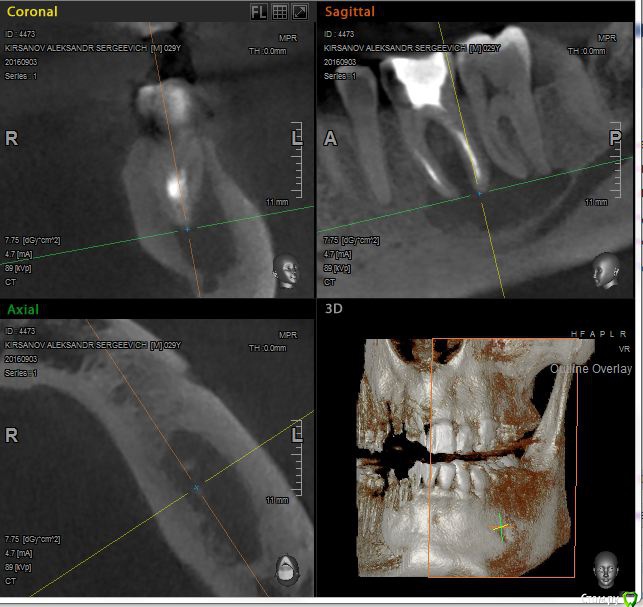

St. Опубликовано 12 ноября, 2016 Поделиться Опубликовано 12 ноября, 2016 Выложу скрины приложенного КТ. Так ответов будет больше. Есть пропущенный канал в 6 зубе. И нужно проверить на жизнеспособность соседний 7. Я бы рекомендовала попробвать перелечить и понаблюдать. Но Вы должны для себя понимать что перелечивание каналов очень сложная, дорогая и непрогнозируемая процедура. Хотя вероятность успеха достаточно высока. Если хотите гарантий - тогда удаление и имплант как восстановится кость. Еще хорошо бы знать как давно лечили каналы в этом зубе, как он вел себя после лечения, беспокоит ли сейчас? 2 Ссылка на комментарий

St. Опубликовано 12 ноября, 2016 Поделиться Опубликовано 12 ноября, 2016 11, 21 по кт без особенностей. Так что артефакты скорее всего. В 23( левый клык) есть тоже воспаление на корне. Нужно планово перелечиавать. Ссылка на комментарий